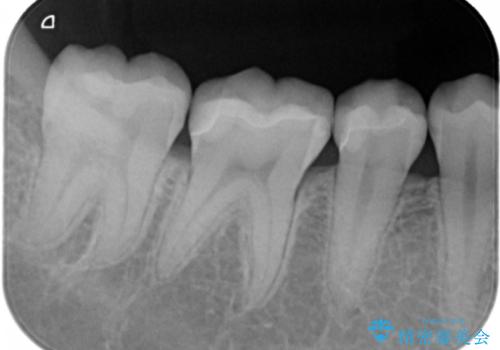

隠れているむし歯 セラミックインレーによる治療

- 2年ぶりの来院。メンテナンス時に虫歯が多数確認されました。

まずは虫歯の大きいところから治療を進めることになり今回は右下の奥歯の治療を行いました。

- 右下56 セラミックインレー 77000円×2本費用は治療当時の料金となります

メンテナンスで虫歯を発見することができたため、症状が出る前に治療を終えることができました。下の奥歯は笑った時に外からよく見える部分なので白く目立たない詰め物を入れることができて大変喜んでいただけました。

放置していくとインレーでの修復が難しくなってしまうため、定期的なメンテナンスが大事になってきます。